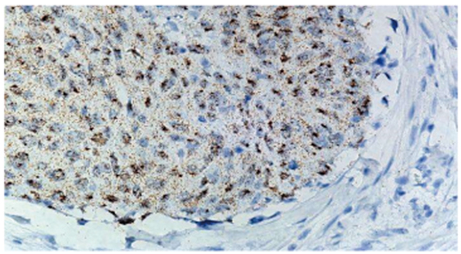

RNAscope™ は、FFPE 組織、凍結組織、培養細胞等のサンプル中の RNA 局在を、独自のシグナル増幅法を用いた RNA ISH(RNA in situ ハイブリダイゼーション)法により高感度に可視化する技術です。

低発現遺伝子の検出・定量にも対応し、シンプルなワークフローで特異性も高く、論文掲載実績も年々増加しており、2025年6月には13,000報を突破しました。ISH 定量解析まで見据えた研究に最適です。

従来のDigoxigenin-ISH法よりも100倍以上高感度

分子のRNAを1ドットとして検出可能